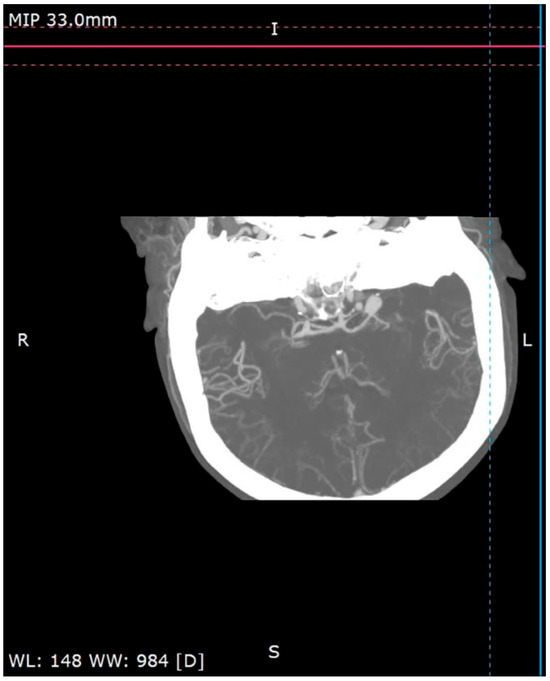

A 58-year-old woman treated for exudative pericarditis (effusion up to 6 mm) for the last 6 months was referred to a hepatologist/infectious diseases specialist with hypoechoic unclear lesions in the liver due to suspected hepatic tumor. Computed tomography confirmed simple hepatic cysts, while blood analysis revealed significant eosinophilia (23.4% in percentage, normal range 1–6%; eosinophil count: 1.45 in thousand eosinophils per microliter (K/μL), normal range 0.02–0.5 K/μL). The patient denied any symptoms, such as fever, abdominal pain, weight loss, cough or diarrhea in recent months; however, she described left-sided subjective eyeball enlargement, pain and redness. Her history included travels to Mexico, Egypt and Tunisia, as well as occasional raw meat consumption in Poland. She also had a dog, which did not receive regular parasite screenings and preventive medications. Her father had died from liver cancer. Lab tests confirmed the presence of IgG antibodies against Toxocara canis and sustained eosinophilia (18.1% in percentage, normal range 1–6%; eosinophil count: 1.01 in thousand eosinophils per microliter (K/μL), normal range 0.04–0.4 K/μL). Echinococcosis was excluded based on negative serology. Diagnosis of toxocariasis was further supported by clinical manifestations and exposure history with positive serology, and the patient was treated with mebendazole (200 mg twice a day for 5 days). Due to the suspicion of an ocular parasitic invasion, she was sent for an ophthalmological consultation. The ophthalmological examination was inconclusive, but head MRI revealed vascular abnormalities in brain arteries. CT angiography confirmed four aneurysms with one causing the constriction of an artery supplying the left eyeball (Figure 1, Figure 2 and Figure 3): two cerebral aneurysms of LICA (left internal carotid artery) size: 4.2 × 8.7 × 3.5 mm and 9.8 × 7.8 × 10.7 mm, one cerebral aneurysm of LMCA (left middle cerebral artery) size: 3.5 × 3.3 × 3.2 mm and the fourth enlargement for differentiation between an aneurysm and an infundibular dilations (3 mm) of LMCA. Clipping the aneurysms dissolved the ophthalmological problems. During the last check-up, normalization of the eosinophil count, full resolution of the ocular symptoms and no pericardial effusion were seen, further supporting our diagnosis of visceral toxocariasis. Hepatic cysts began to disappear. The patient was recommended to perform an abdominal ultrasound every 6 months.

Figure 2.

Cerebral 3D CT angiography.